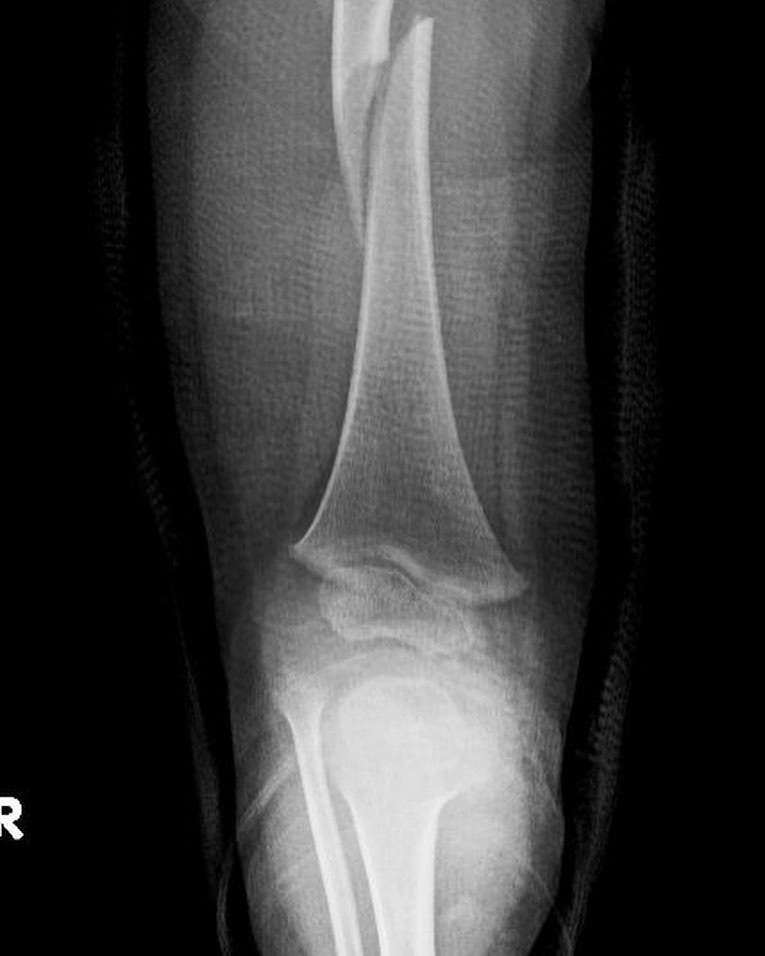

Fractura de fémur

El año pasado mi pacientito Dylan se fracturó el fémur, realizamos tratamiento conservador y ahora está al 💯 Vino a consulta y recibí este delicioso regalo, ¡muchas gracias Dylan!